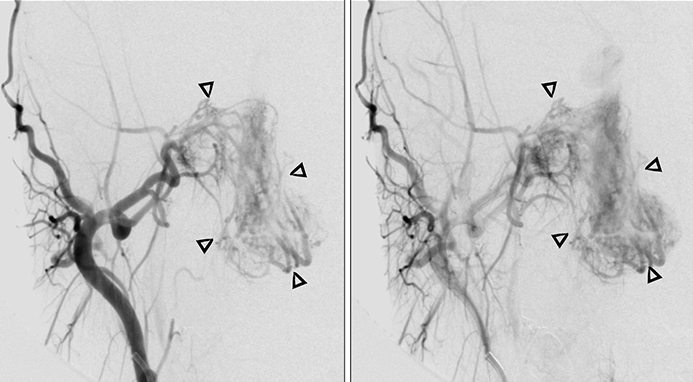

Aνάλογα με το μέγεθος και τις επεκτάσεις, αιματώνονται από διάφορετικές αρτηρίες. Στο αρχικό στάδιο που ο όγκος εντοπίζεται στον πρόσθιο ρινοφάρυγγα και την οπίσθια ρινική κοιλότητα, η αιμάτωση γίνεται από το τελικό τμήμα της έσω γναθιαίας αρτηρίας (με τον σφηνουπερώιο κλάδο να τροφοδοτεί το ρινικό τμήμα, και τον πτερυγοειδή κλάδο το ρινοφαρυγγικό τμήμα του).